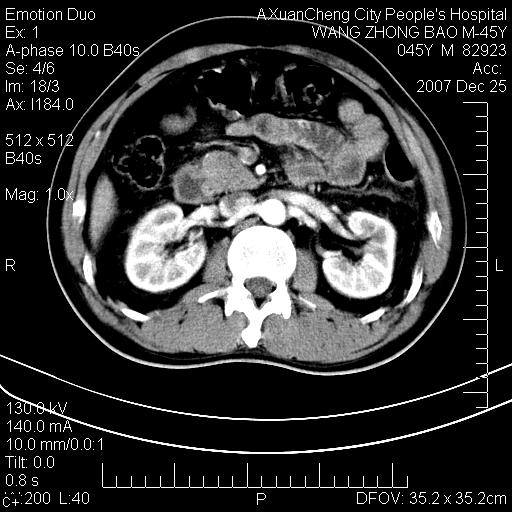

以下是引用qiuleiyu在2007-12-25 18:14:00的发言:[br]胰腺增大,周边渗出改变,肾前筋膜明显增厚,示少量积液.胆囊壁毛糙,周边少许渗出,胆总管壁厚,异常强化,然扩张不明显.结合病程急短;考虑;胆管炎,胆囊炎,胆源性胰腺炎可能大,请结合实验室检查及随访.

以下是引用lisihao在2007-12-25 14:23:00的发言:[br]急性水肿型胰腺炎[br]依据:1、胰腺弥漫性肿大,边缘稍毛糙;[br] 2、双侧肾周筋膜增厚,尤以左侧为甚(重要征象)[br] 3、双侧后胸膜增厚(刺激性炎症);[br] 4、结合病史,查血尿淀粉酶应该可以确诊。